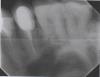

rasin Опубликовано 2 марта, 2013 Поделиться Опубликовано 2 марта, 2013 Уважаемые доктора! Прошу оценить по снимку качество прилегания МК коронки на 15 зубе. Коронка установлена меньше месяца назад. Сразу после установки заметила, что из промежутка 15-16 ирригатор вымывает что-то с неприятным запахом (видимо, остатки пищи). В других межзубных промежутках такого нет.Буду благодарна всем откликнувшимся. Ссылка на комментарий

dok1 Опубликовано 2 марта, 2013 Поделиться Опубликовано 2 марта, 2013 Вариант один, переделка. Проблема из-за слабого точечного контактного пункта коронки с соседним зубом. Переделывайте, пока карман не образовался. Ссылка на комментарий

dok1 Опубликовано 2 марта, 2013 Поделиться Опубликовано 2 марта, 2013 Снять проблем нет - распилить аккуратно и всё. Техник не создал контактный пункт должным образом - не критично. После примерки доктор ему должен был указать на это техник к следующему визиту всё поправил бы. Но доктор пропустил и зафиксировал как есть. Делайте выводы. Вообще переделка по гарантии. По идее проблем не должно быть. Ссылка на комментарий